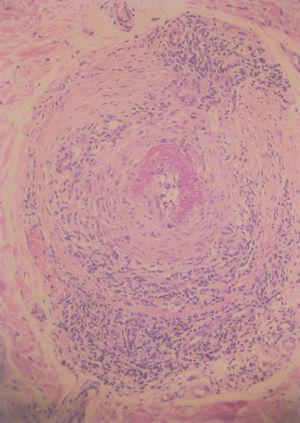

Fig. 3.--Arteritis de un vaso de mediano tamaño localizado en dermis reticular profunda. (Hematoxilina-eosina, x20.)

Fig. 4.--Detalle histológico de la arteritis con infiltración linfocitaria. (Hematoxilina-eosina, x40.)

En la biopsia cutánea se apreciaba una arteria de mediano calibre en la porción inferior de la dermis reticular, con un infiltrado predominantemente linfocitario dispuesto entre y alrededor de las capas de la arteria. La arteria presentaba signos de necrosis fibrinoide (figs. 3 y 4).

En el estudio anatomopatológico se aprecia una arteritis de vasos de mediano calibre dispuestos en la dermis reticular profunda y el tejido celular subcutáneo, predomina un infiltrado neutrofílico asociado en ocasiones a necrosis fibrinoide y vasculitis leucocitoclástica. Los polimorfonucleares se sitúan en la pared del vaso donde se observan depósitos de material fibrinoide 10.